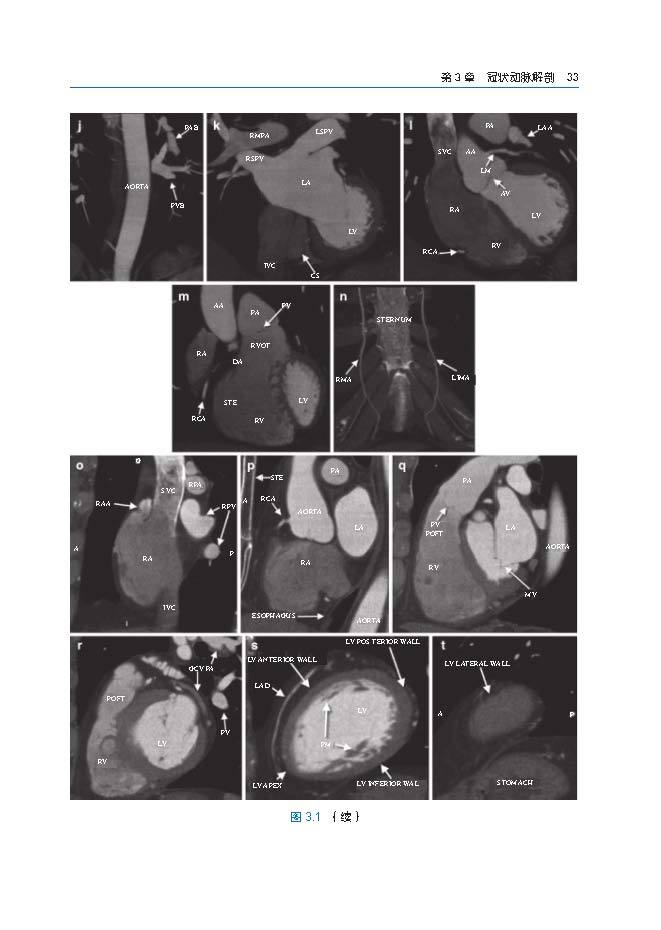

本书涵盖多种心脏冠状动脉病例,每个病例都包括精细的CTA图像、简短的病史报告、检查、诊断、讨论、经验和教训,分析正常冠状动脉解剖、先天冠状动脉发育异常、冠状动脉性疾病、经皮冠状动脉治疗、心脏外科血运重建术后改变,以及除冠状动脉以外的心-胸血管发育异常。在第1版的基础上,新增关于心脏CT的操作及报告原则、心肌病、儿童心脏病、急诊心脏CT应用、源自CT的血流储备分数的章节。本书旨在帮助心血管及影像科医生、心脏内科医生和心胸外科医生了解与冠状动脉CTA的临床及后续干预的一系列问题,图文并茂,内容翔实,具有很强的实用性。

本书涵盖多种冠状动脉疾病CTA病例。其影像分析包括正常冠脉解剖、先天冠脉发育异常、冠状动脉性疾病、经皮冠状动脉治疗、心外科血运重建术后改变,以及除冠状动脉以外的其他心胸血管发育异常。